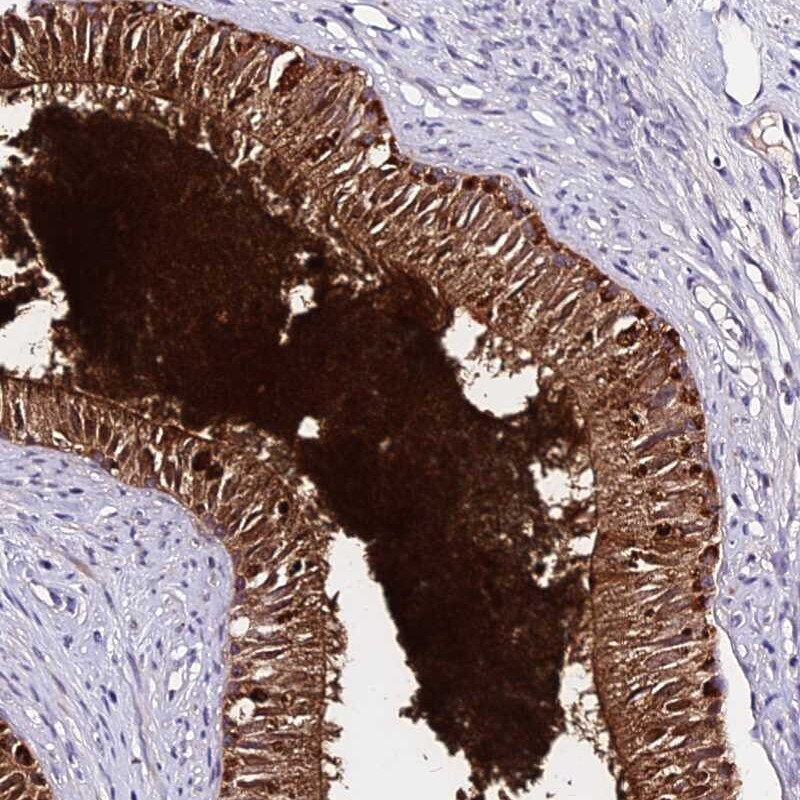

- Immunohistochemical analysis of DEFB106A in human epididymis using DEFB106A Polyclonal Antibody (Product # PA5-61041) shows strong positivity.